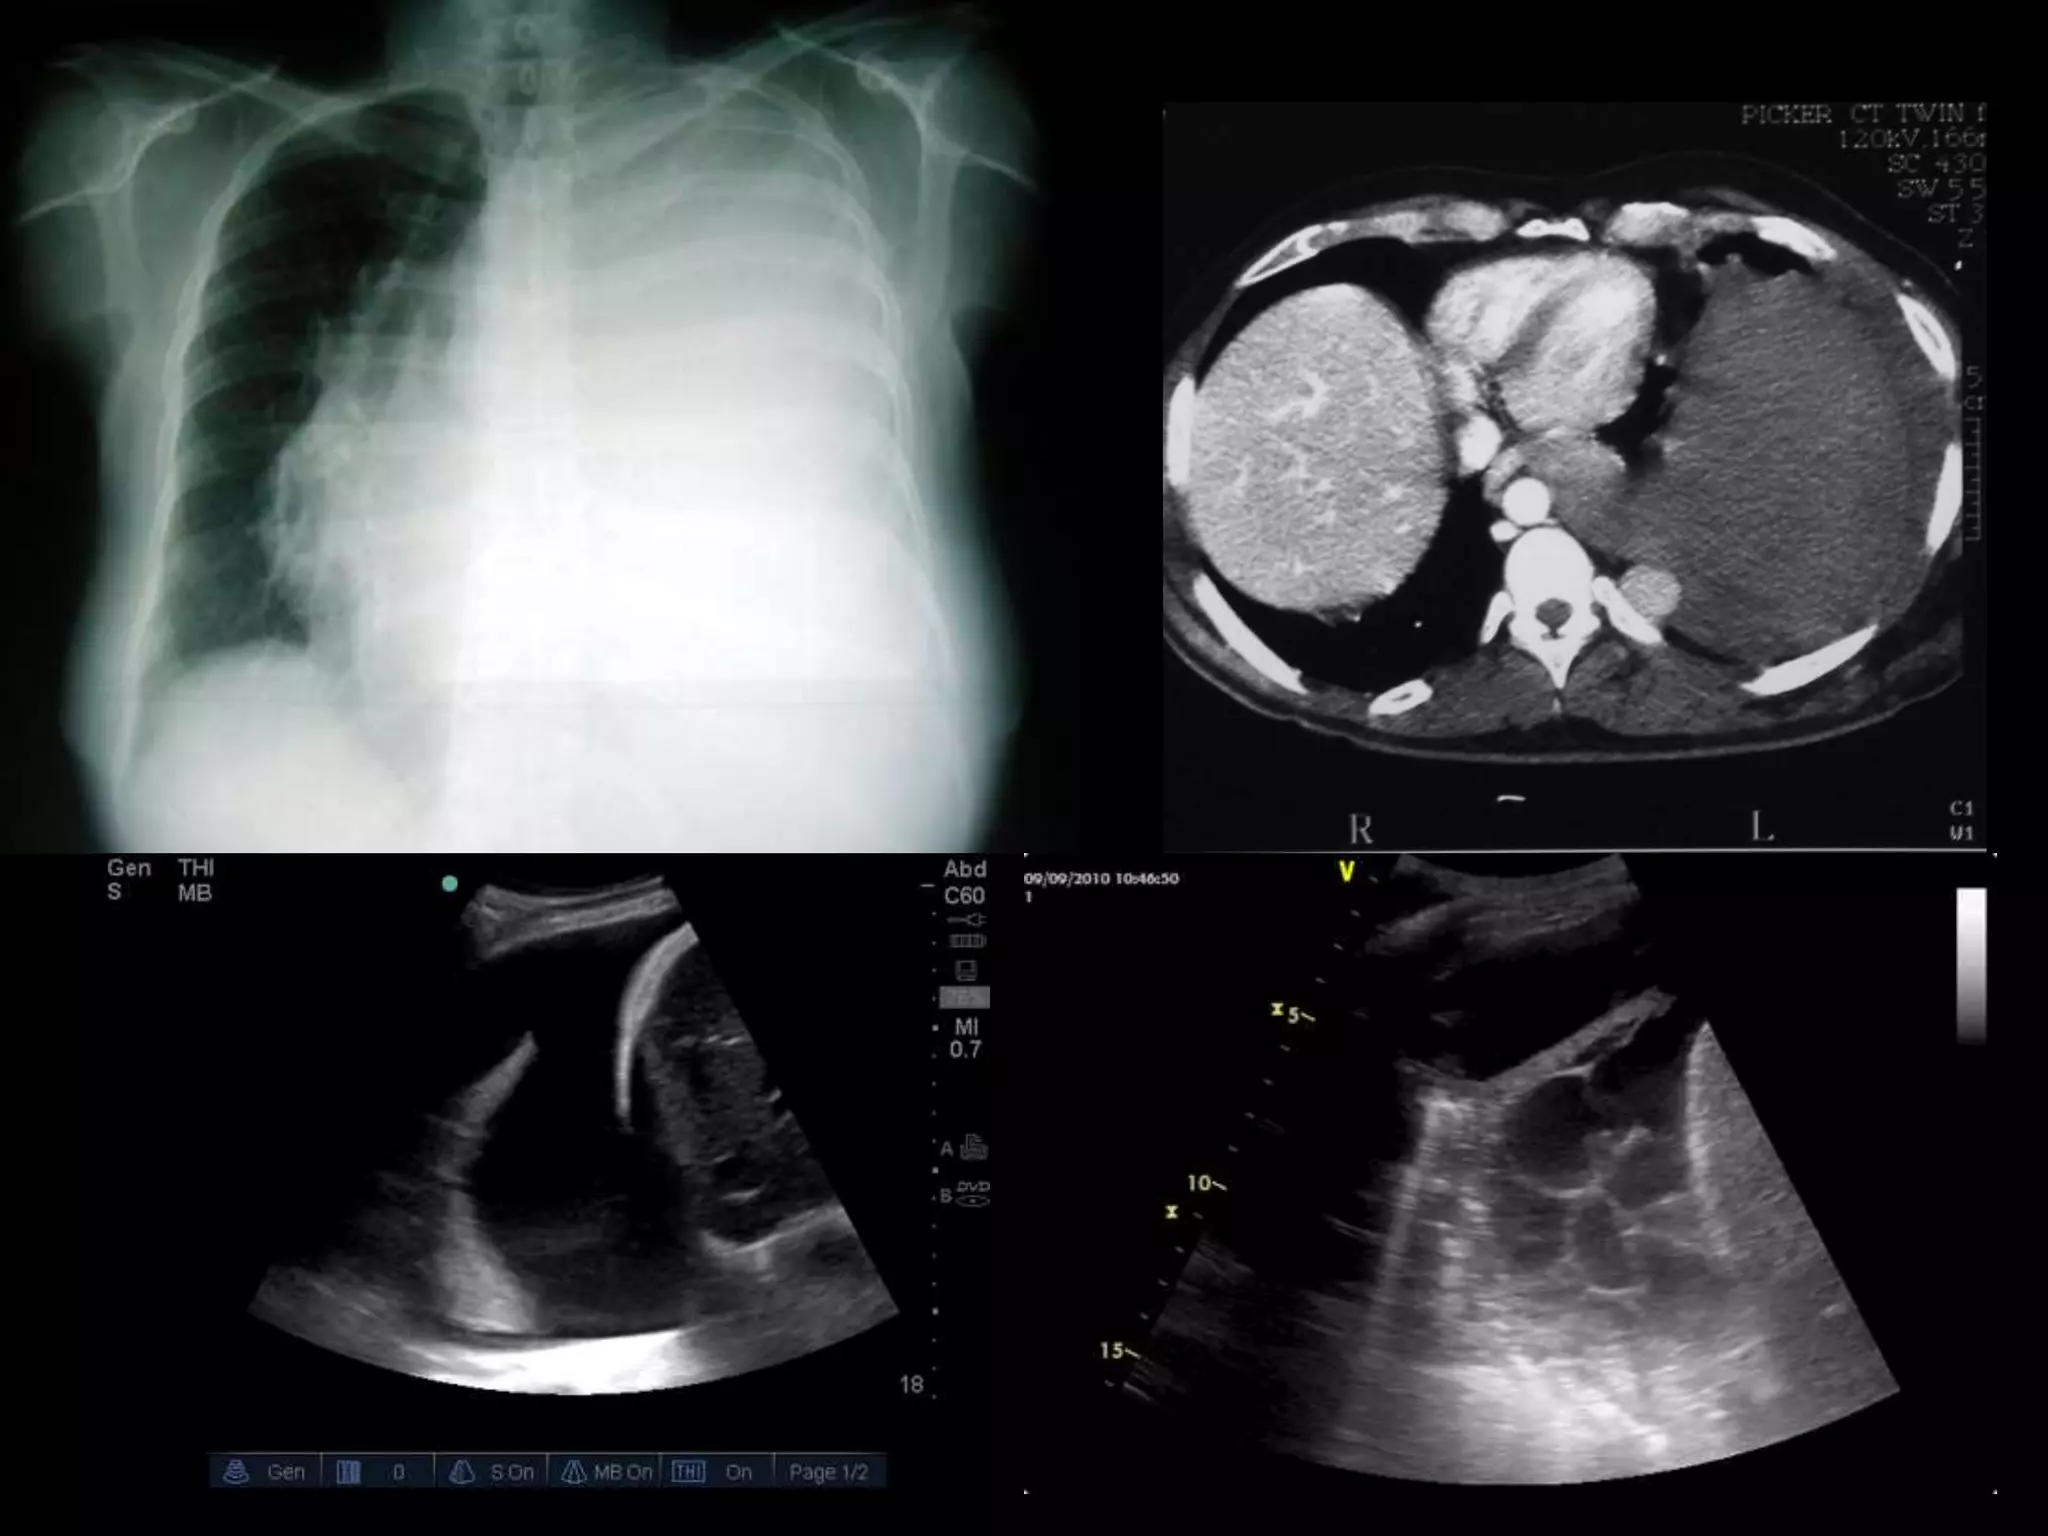

Este documento proporciona una lista de términos radiológicos relacionados con el tórax y los pulmones. Incluye descripciones breves de diferentes patrones de opacidad pulmonar como consolidación, neumotorax, nódulos y cavernas, así como sus posibles causas. También cubre términos relacionados con el mediastino y las técnicas de imagen torácica.